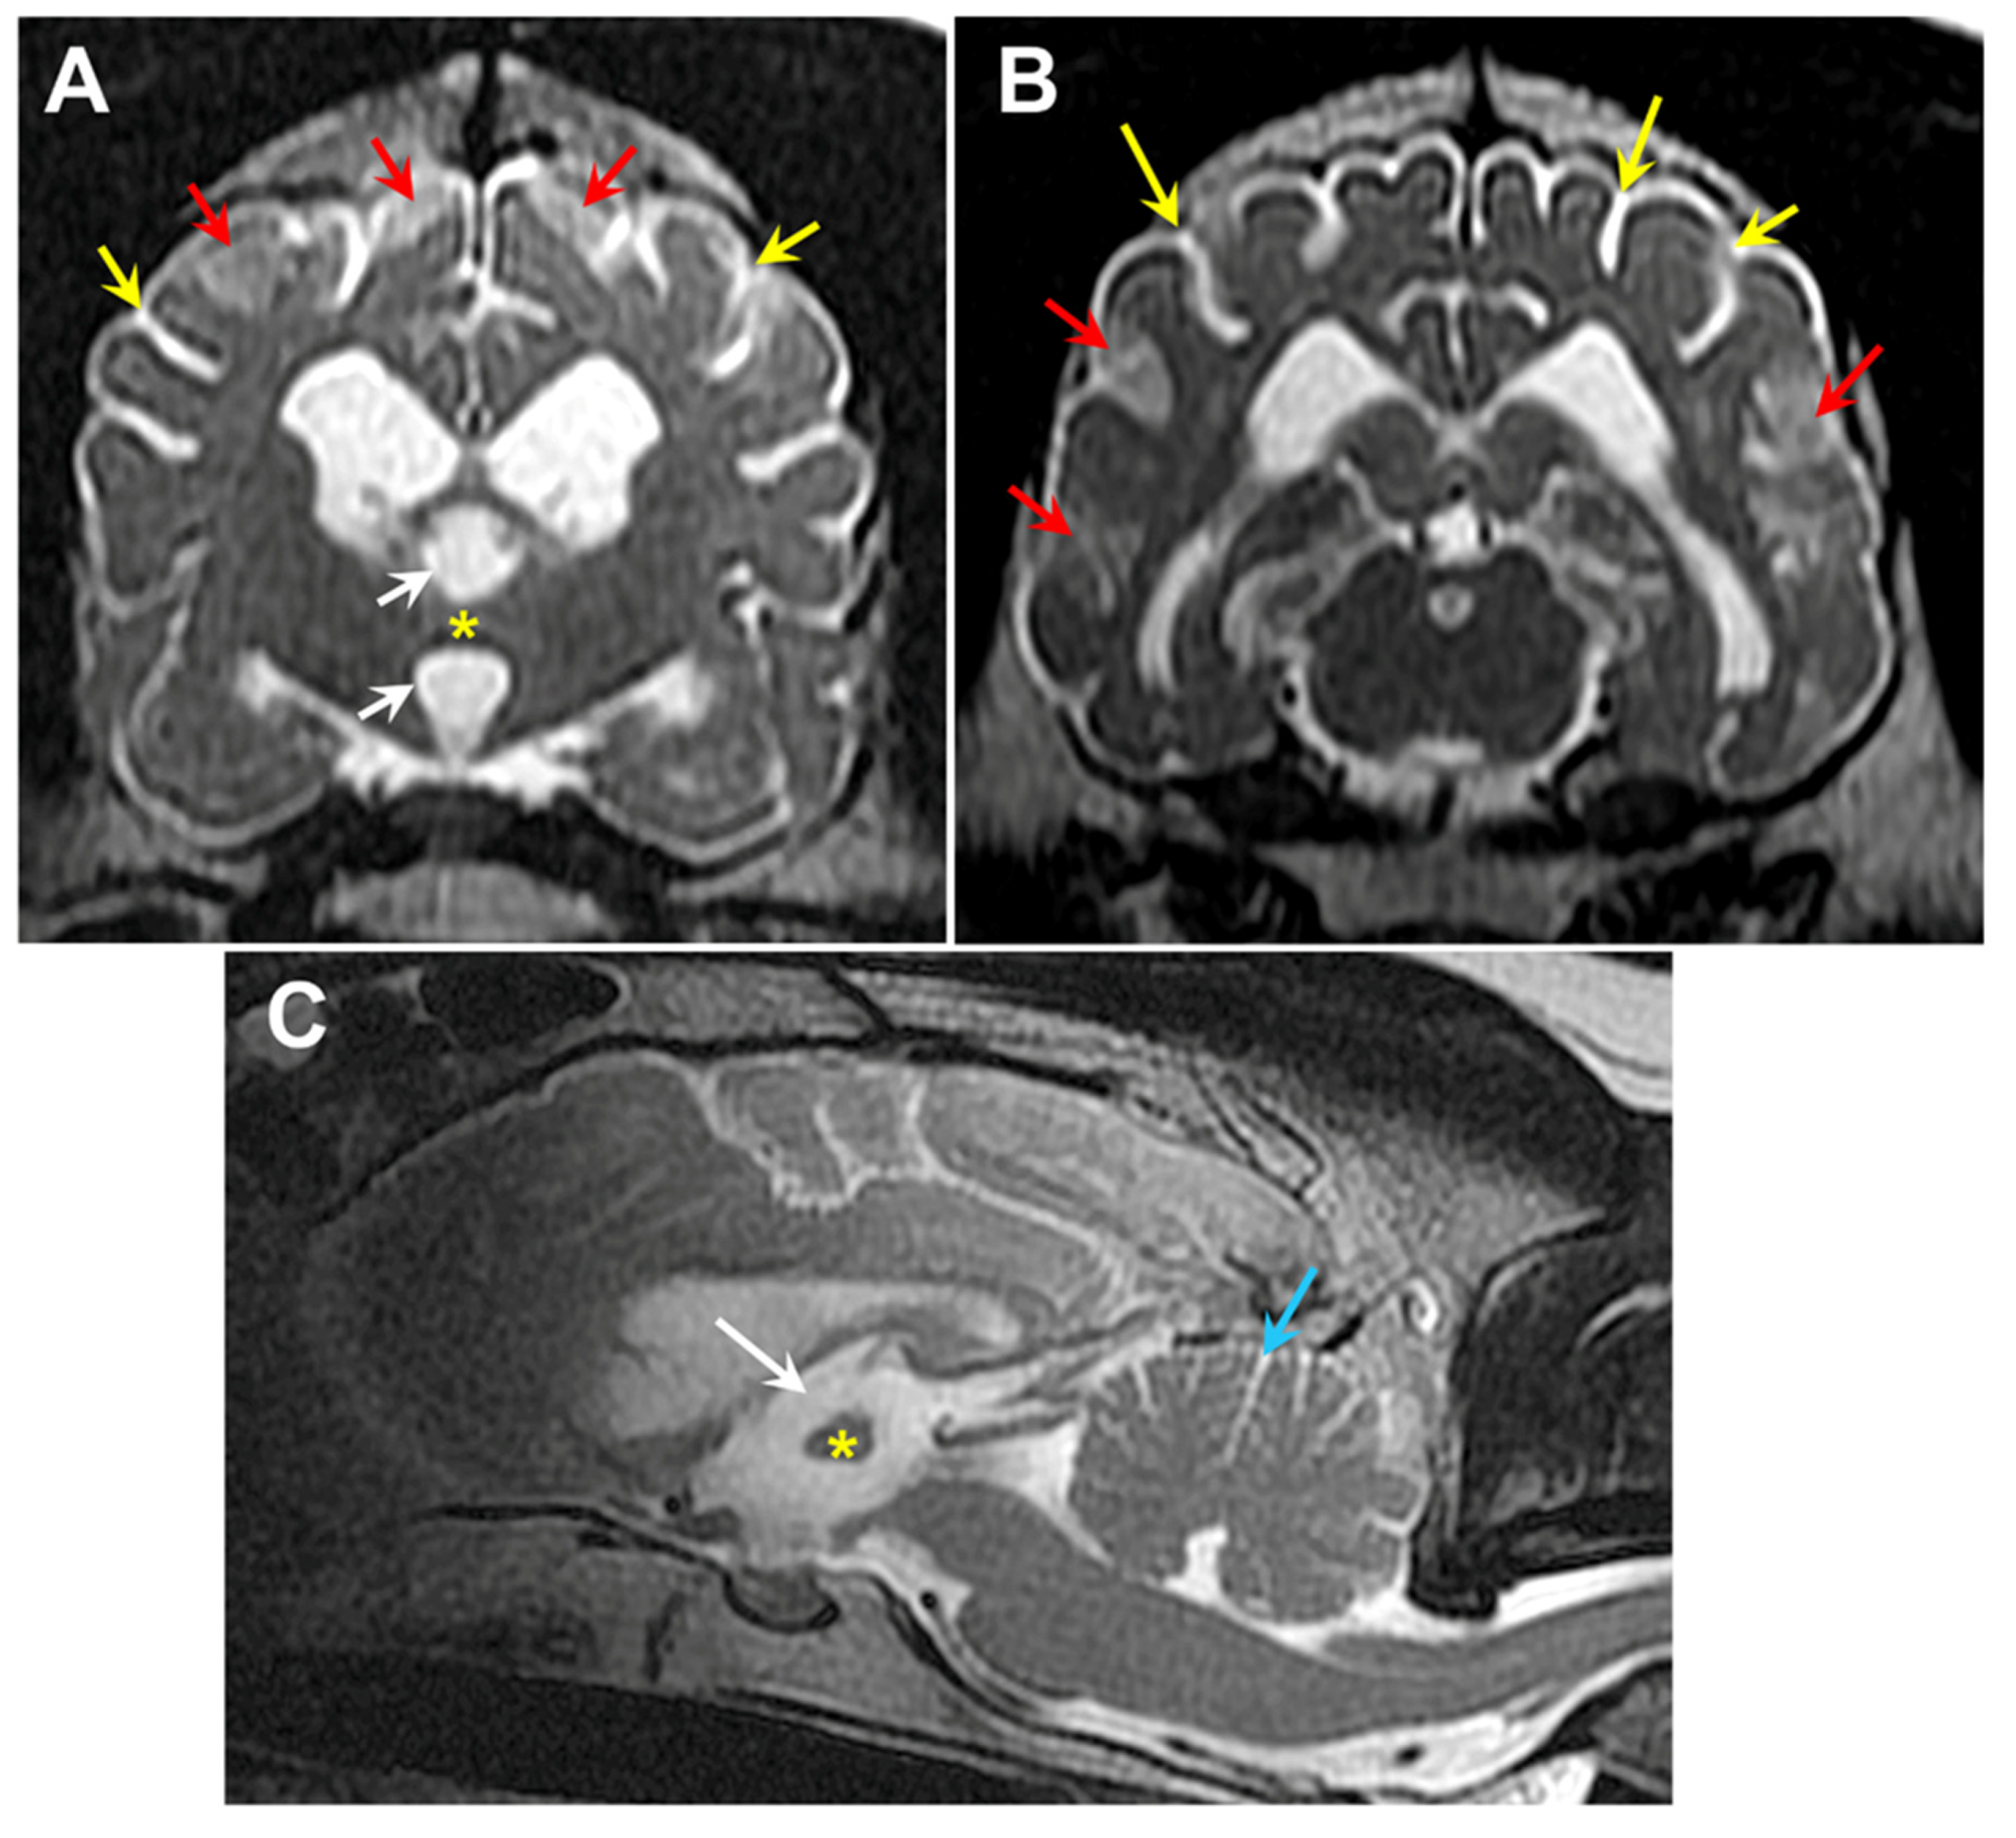

Figure 25. T2-weighted MR images of the brain from Dog 2: transverse views at the level of the interthalamic adhesion (A) and at more caudal location (B), and a saggital view (C). The dog exhibited cerebral parenchymal atrophy characterized by an abnormally small interthalamic adhesion (yellow asterisks), an enlarged third ventricle (white arrows), and widened cerebral cortical sulci (yellow arrows). Increased CSF volume between the cerebellar folia (blue arrow) was indicative of cerebellar atrophy. The dog also exhibited multiple areas of increased signal intensity within the cerebral cortex parenchyma (red arrows).

Two hundred-ninety-two of our archived DNA samples from Weimaraners were genotyped for the 9:20,355,460 G/A polymorphism in CNP. In addition to the proband, one other sample tested homozygous for the variant 9:20,355,460 A allele. The homozygous sample was from a spayed female that exhibited bilateral hindlimb weakness and fecal incontinence. The sample was submitted to us to evaluate a differential diagnosis of degenerative myelopathy [8], which was ruled out when the sample tested homozygous for the reference G allele at 31:26,532,306, the site of the G-to-A transition in SOD1 associated with degenerative myelopathy in many breeds [9,10]. When 8 years old, this Weimaraner presented for a 5-week history of pelvic limb weakness which started after stumbling down the stairs and a one-year history of progressive fecal incontinence (dropping stools 2-3 times a week). The initial examination identified an ambulatory paraparesis and generalized whole body tremors noted at rest and during movement (a pre-existing condition present since puppyhood). T2 magnetic resonance images of the neuraxis demonstrated significant generalized brain atrophy and areas of increased signal intensity in the cerebral cortex parenchyma similar to those observed in the proband (Figure 25). Cerebrospinal fluid analysis and cytology indicated a marginal increase in protein concentration (46.0 mg/dL, upper limit RR 45mg/dL) and normal nucleated cellularity and cell types. Genetic testing for variants previously associated with hypomyelination or spinal dysraphism demonstrated no mutations [11,12]. The patient was initially started on azathioprine (25 mg PO SID) as an empirical immunomodulatory therapy for suspected immune mediated inflammatory myopathy/ polyneuropathy. Azathioprine was then discontinued due to increased hepatocellular enzyme values and cyclosporine (100 mg PO SID for 30 days), a tapering dose of prednisone (15mg PO SID for 14 days to start), and Cerenia (30 mg PO SID PRN) therapy was initiated. Ten-months later the patient was again evaluated for increased symmetrical muscle atrophy, worsening pelvic limb paresis and generalized whole body tremors at rest and during movement or weight bearing. Because of progression in her clinical signs, the patient was euthanized, but no necropsy was performed.